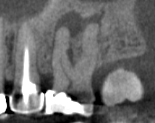

CBCT Scans provide a 3D dental image, while traditional X-rays are only a 2-dimensional picture of the mouth. This means that with traditional X-rays alone, it is very difficult to diagnose non-painful lesions like dental abscesses that are within the jaw bone.

Here are some examples of photos of bone lesions

Patient “A ”Xray of a root canal tooth #14 CBCT Scan of same tooth #14, notice the lesion on the bone at the tip of the left root Notice root canal #13 on xrays CBCT Scan on same tooth #13, there is a lesion at the tip of the root causing sinus membrane inflammation. Patient “C” xray tooth #14 Patient “C” CBCT Scan tooth #14, bone lesion affects both roots. Upland Lighthouse Dentistry, a renowned family dentist in Upland, offers cone beam CBCT scan technology for comprehensive dental care. Our expert dentist utilize this advanced 3D imaging technique to obtain precise details of dental structures, soft tissues, and nerve paths, enhancing our diagnostic accuracy and treatment planning. Contact Upland Lighthouse Dentistry today!